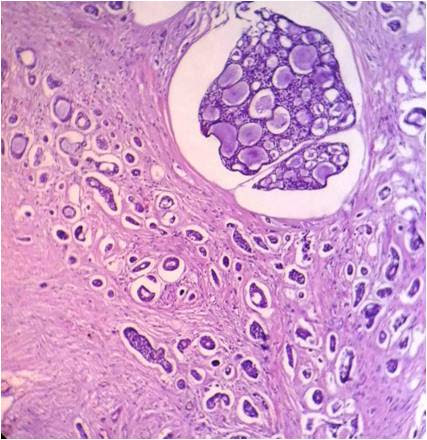

Ameloblastomas are benign tumors whose importance lies in its potential to grow into enormous size with resulting bone deformity.[28] Basal cell ameloblastoma is a rare variant of solid multicystic ameloblastoma (SMA) with only 11 cases reported in the literature so far.[29] Clinically they are similar to other histopathological variants of SMA.[29],[30],[31] Histopathologically, they exhibit nests of basaloid cells that show intense basophilic staining.[29] The stellate reticulum-like cells are absent and central cells may be polyhedral.[29],[30] The nuclear orientation of peripheral cells is different from the other histopathological patterns of ameloblastomas: they are usually cuboidal or columnar and do not show reverse polarity (Figure 4). BCAs show a close resemblance to BCC on histopathology; however a demarcation can be made on immunohistochemical grounds by using Ber-EP4.[29],[30] The prognosis and biological behavior of BCA is not clear, due to its rarity and very few reported cases.

Figure 4. Sheets of basaloid cells with few cells showing highly intense basophilic staining and peripheral cells with reversal of polarity, the sheets are separated by sparse connective tissue septa. The tissue is lacking stellate reticulum like cells which is the hallmark of ameloblastoma (Hematoxylin and eosin stain x20).